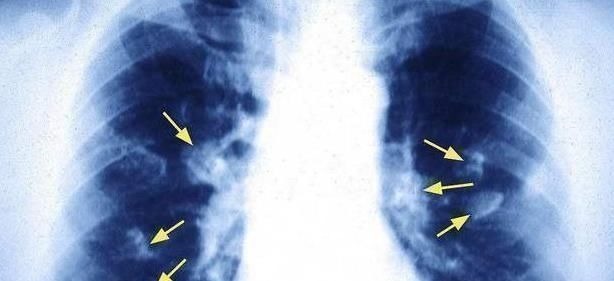

■肺癌来临前,身体也是蜘蛛网痕迹,注意到这四种身体表达!●不明原因的疼痛:在日常生活中,肺癌可能会像其他癌症一样,在疾病的早期阶段导致某些疼痛。一些肺癌患者可能会有疼痛。一些肺癌患者表现出明显的疼痛。这种物理疼痛会出现一段时间,然后消失;但是生活中,情况可能会更加严重,半夜可能会醒来。●呼吸会感到疼痛:日常生活中较明显的早期肺癌症状之一是患者经常会觉得自己的肺部隐隐不适,或者有点明显。健康的肺没有疼痛和不便。这种情况主要是肺部受损,平时呼吸时肺部也参与呼吸过程,这时肺部吸入氧气和吐出二氧化碳时,会出现异常症状和疼痛。

●长期严重咳嗽:日常生活中,倘若你身体内的肺部出现了炎症问题,并且有长期生活在环境不好的地方,那就很容易导致肺癌的风险增加。在肺癌早期阶段,患者很容易就会表现为十分剧烈的咳嗽问题,而肺癌所引起的咳嗽跟我们常见感冒或是呼吸道感染所引起的咳嗽有所不同;肺癌所引起的咳嗽问题,通常都是持续较长一段时间,特别是凌晨的时候,这种咳嗽会变得更加明显和剧烈,后期随着肺癌不断的发展,患者甚至会无休止的不停咳嗽。●尿液颜色异常:对于患上肺癌的朋友而言,由于体内的肺部被癌细胞所侵害,所以会受到极大的损伤,这样就会导致体内的器官组织受到牵连,从而产生病变问题。这个时候就会导致患者在平时排尿时出现异常,比如无论你喝了多少的水,尿液都是黄色的;并且平时排便时,大便也会变成柏油状的黑色。而生活中的尿液和粪便出现这些情况,那么还请及时去医院就诊检查。